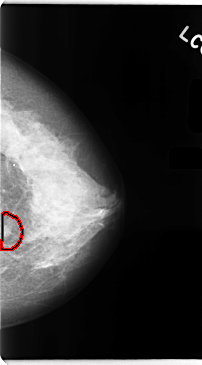

C_0104_1.LEFT_CC

FILE: C_0104_1.LEFT_CC.OVERLAY

TOTAL_ABNORMALITIES 1

ABNORMALITY 1

LESION_TYPE MASS SHAPE IRREGULAR MARGINS SPICULATED

ASSESSMENT 5

SUBTLETY 5

PATHOLOGY MALIGNANT

TOTAL_OUTLINES 1

BOUNDARY